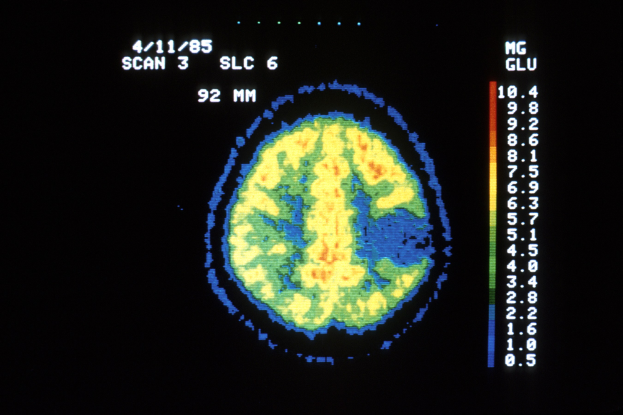

Die Idee zu StrokeCap entstand durch PD Dr. Stefan Herz und Dr. Patrick Vogel, die zuvor an MPI-basierten Tomographen arbeiteten, bevor sie das Konzept verfeinerten. Ihr Gerät injiziert magnetische Nanopartikel in den Blutkreislauf, sodass Ärzte die Durchblutung des Gehirns sofort visualisieren können. Im Gegensatz zu herkömmlichen Methoden kommt es ohne Strahlung aus und lässt sich sogar im Rettungswagen einsetzen – was schnellere Behandlungsentscheidungen ermöglicht.